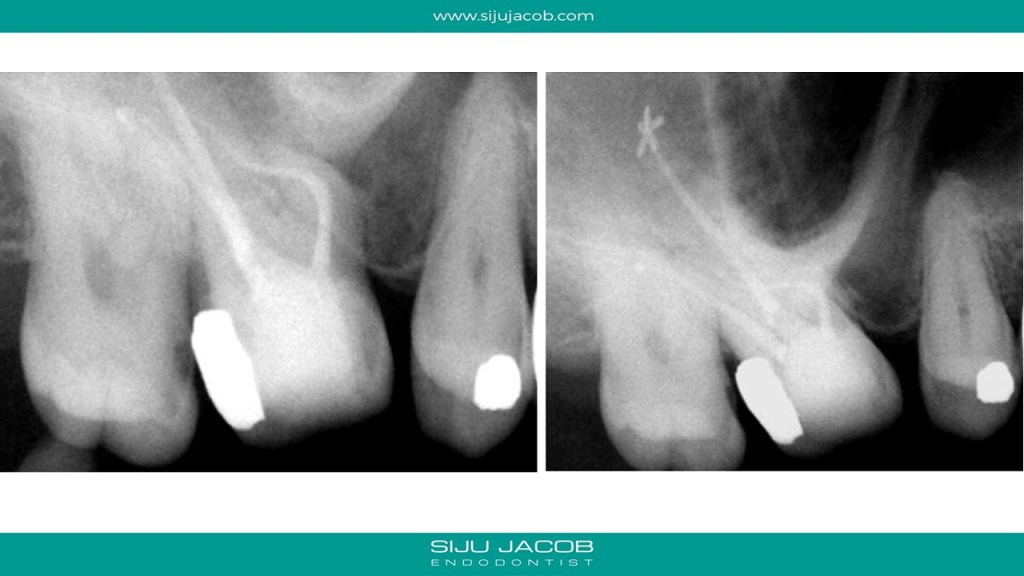

The Mesio-buccal canal in this tooth was probably the most curved canal I ever treated. It went straight initially, then took a left turn, then a right, then a left again to exit. And to add to the Drama, it was before Christmas holidays and the palatal root ended up with sealer pushed apically in the shape of a proper Christmas Star. Bizarre! π